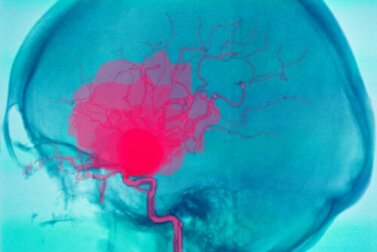

L’emorragia cerebrale mette a rischio la vita della persona. Consiste in un versamento ematico nel cervello, che provoca un travaso di sangue e impedisce a quest’ultimo di raggiungere adeguatamente tutte le parti dell’organo.

Rappresenta la seconda causa di ictus, o accidente cerebrovascolare. La mortalità da emorragia cerebrale, nonostante i trattamenti oggi disponibili, continua a essere molto elevata. Chi sopravvive, inoltre, presenta spesso complicazioni.

Un’emorragia cerebrale è un versamento ematico che si verifica all’interno del cervello. Generalmente provoca la brusca comparsa di disturbi neurologici e può perfino condurre al coma.

Ciò si deve alla mancanza di afflusso di sangue alle altre parti del cervello, dal momento che il sangue non è in grado di proseguire il proprio viaggio attraverso i vasi sanguigni. È importante distinguere tra emorragia cerebrale ed emorragia intracranica.